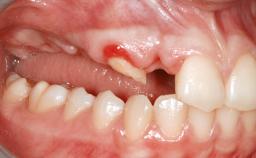

Guided Bone Regeneration (GBR) with a Particulated Autologous Graft and a ePTFE-Reinforced Membrane for Vertical Augmentation of a Single-Tooth Edentulous Space in the Esthetic Zone

A 47-year-old Caucasian woman with a single-tooth edentulous space at the site of the left maxillary canine was referred for treatment. She had undergone traumatic extraction of this impacted canine several months before referral. Her chief complaint was the dissatisfying appearance of her smile. The patient desired a stable and esthetic rehabilitation of the site. Her dental history showed no evidence of periodontal disease or bruxism. She had no systemic diseases, was not taking any medications, and did not smoke. The extraoral examination revealed a high lip line and an inadequate soft-tissue volume at the defective canine site. Large black triangles were visible between the canine and its adjacent teeth.

| Soft Tissue Anatomy | Intact | Defective | |

| Bone Volume | Horizontally and vertically sufficient | Horizontally deficient | Deficient vertically or deficient vertically AND horizontally |

| Soft Tissue Contour and Volume | Significantly deficient |